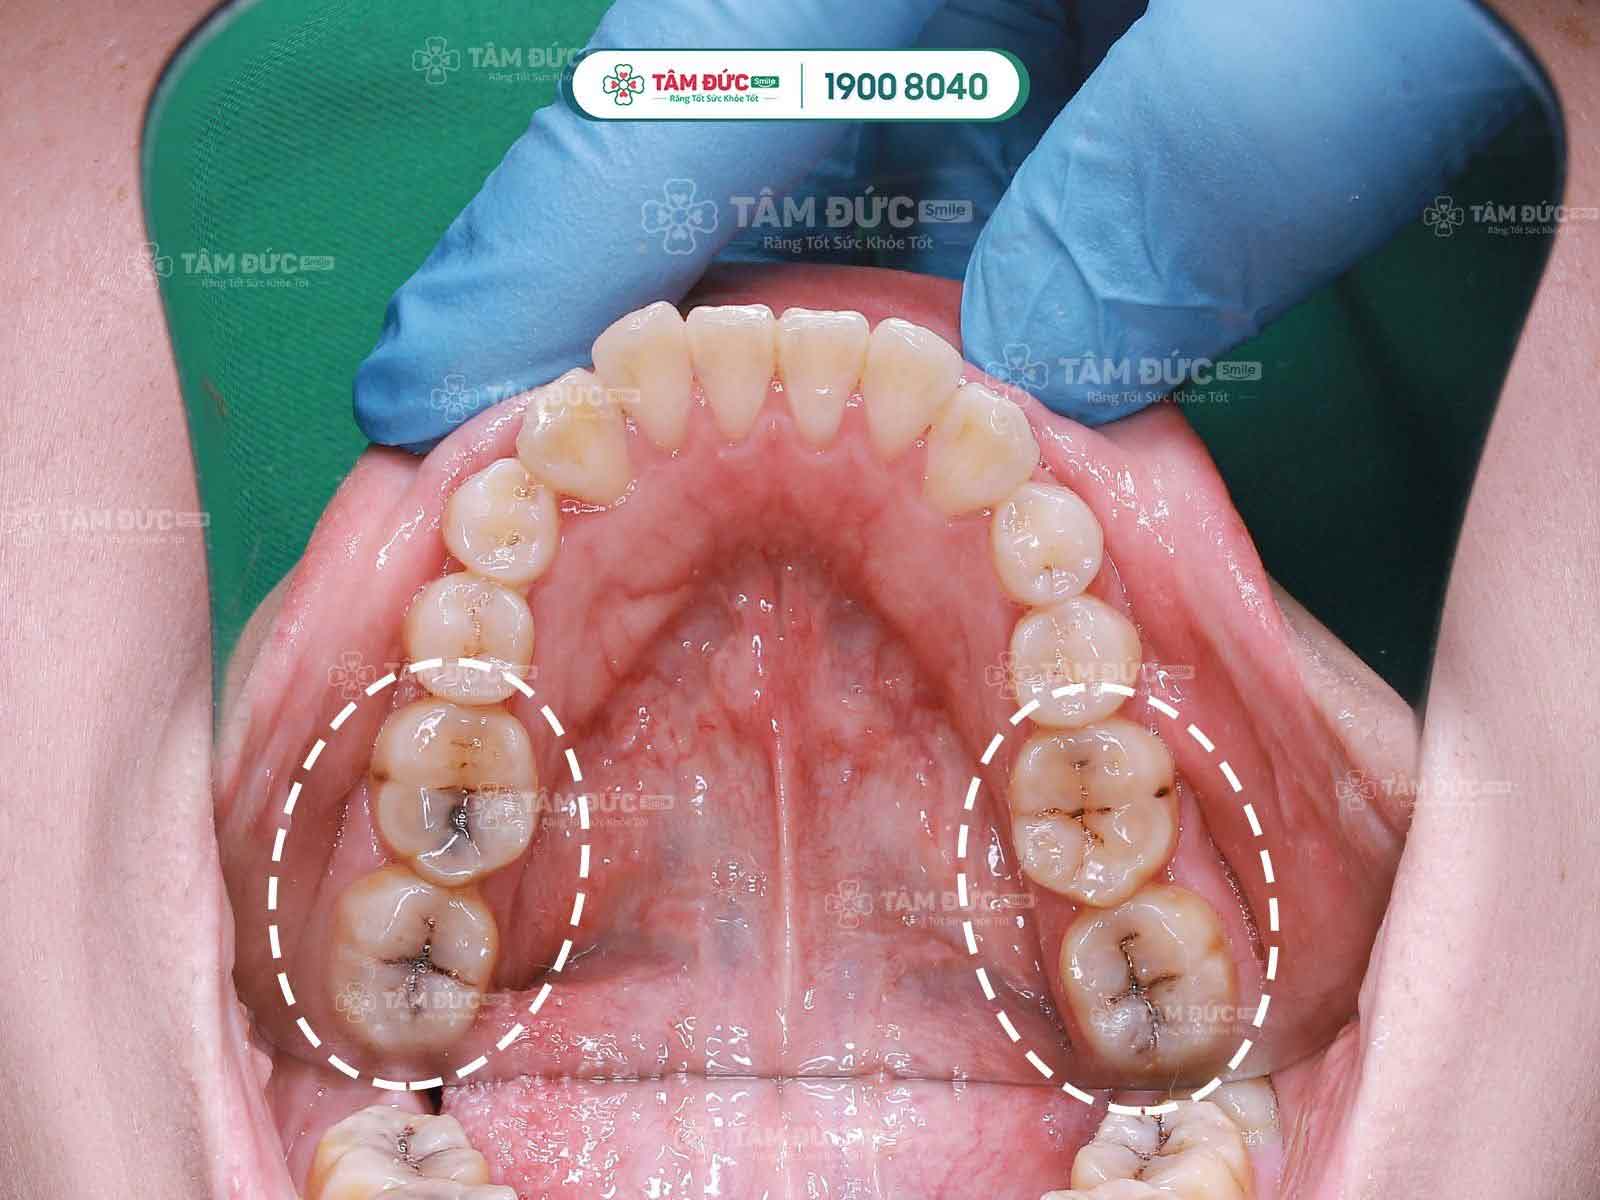

Ê buốt do xiết ăn răng

Răng ê buốt do bị sâu